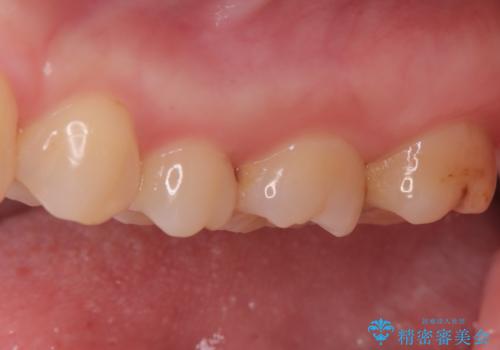

2回で完了した奥歯のセラミック修復

- 奥歯の虫歯治療を主訴にご来院されました。患者様から「できるだけ通院回数を少なく、早く治療を終わらせたい」というご要望があったため、短期間での完了を目指し、セラミックインレー(詰め物)とセラミッククラウン(被せ物)を併用する治療計画を立案しました。治療は精密機器を活用し、2回の来院で最終的なセラミック修復物を装着することを目指します。

今回の治療では、虫歯の大きさや深さに応じて、異なるセラミック修復法を適用しました。

比較的軽度な虫歯には、セラミックインレー(詰め物)で対応し、健全な歯質を最大限に残しました。

進行した虫歯や歯の強度が低下している歯には、セラミッククラウン(被せ物)を選択し、歯全体を保護することで破折を防ぎました。

短期間での治療を可能にしつつ、天然歯と見分けがつかない審美性と、長期的に安定する機能性を兼ね備えたセラミック修復を実現しました。